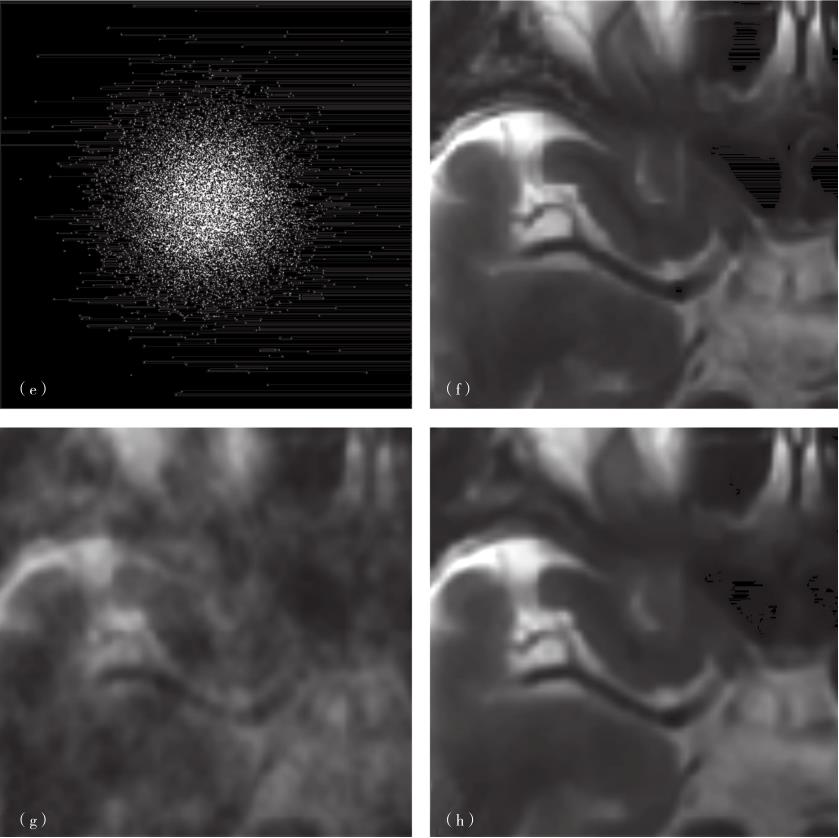

图3-1-4 基于稀疏字典的医学图像重建

(a)k空间信号;(b)原图;(c)欠采样0填充重建结果;(d)基于稀疏字典的重建结果;(e)测量矩阵;(f)是(b)的局部放大图;(g)是(c)的局部放大图;(h)是(d)的局部放大图。

还有一种使用单线圈进行欠采样重建的方式,即压缩感知(compressed sensing,CS)。奈奎斯特-香农采样定理告诉我们,在等步长采样的情况下,若想完整地重建原始信号,采样的点数应当足够多,其对应的采样频率应至少为原始信号中最高频率分量的两倍。压缩感知理论则告诉我们,如果信号在某个变换域中具有稀疏性,则可以使用更少的采样点来重建大部分原始信号。此时的采样方式也未必是等步长采样了。在压缩感知MRI中,最常见的一种采样方式是使用高斯采样矩阵进行采样[图3-1-4(e)]。另外,随着神经网络在图像重建中的不断应用,建立神经网络学习采样矩阵也受到一定关注。